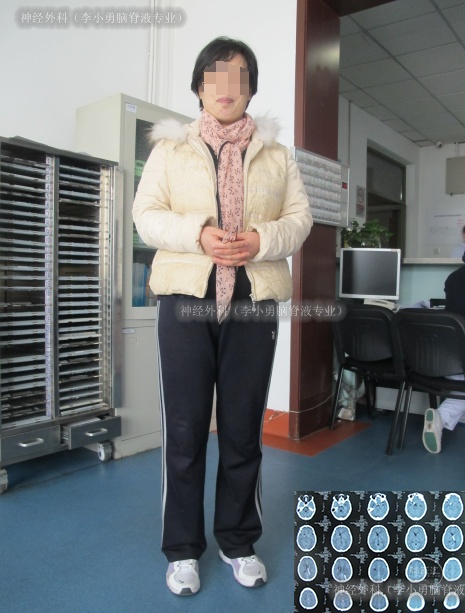

2014年1月20日(即第3家医院治疗21天,又即脑积水分流术并发症进行了49天治疗后仍脑积水、颅内感染),转住入李小勇脑脊液专业,入院时:反应迟钝,张口困难、不能伸舌、不能经口进食,不能言语(图-12);虽可遵命活动肢体但动作微小;右额颞可见长约15cm弧形手术切口疤痕(动脉瘤夹闭手术疤痕);右枕部可见长约5cm纵手术切口疤痕(脑室腹腔分流术疤痕)。颈项强直。双侧瞳孔不等,对光反射迟钝。

图-12:入院时

出院后2月余即2014年5月12日,来院复查时:身体各项机能已恢复至发病前健康的状态(图-19)。

图-19:2014年5月12日